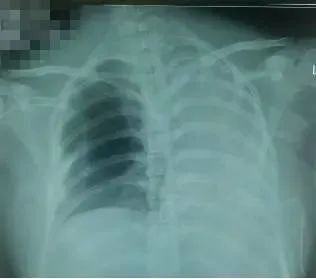

11月23日复查胸片(图4),左肺复张。

图4 ?胸片显示气管插管尖端位于第3胸椎水平,左肺复张